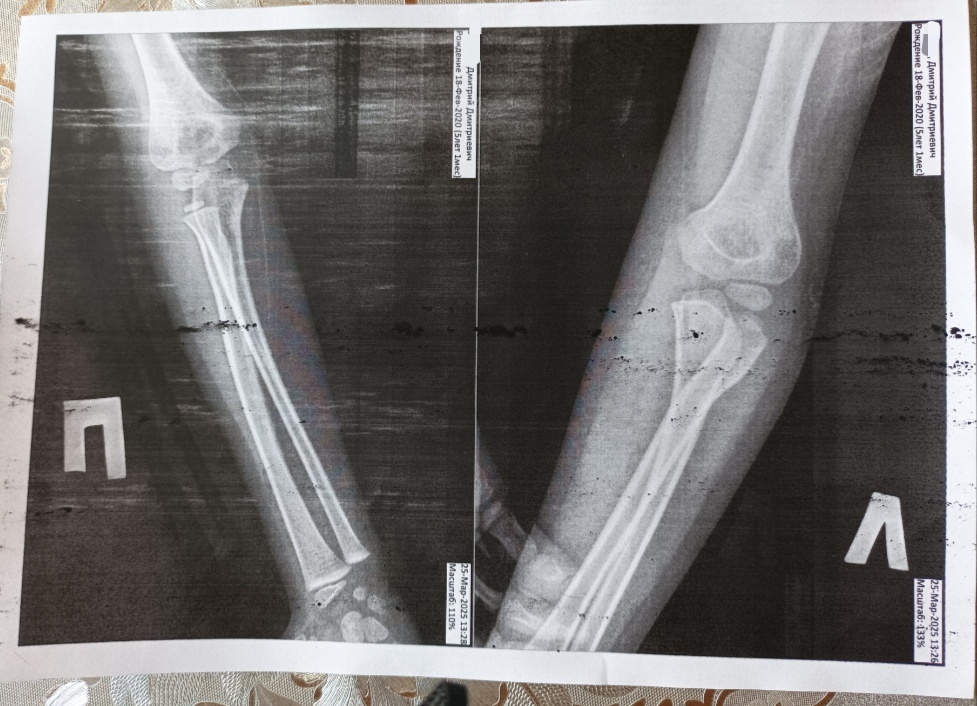

Но всё равно по ним было непонятно, есть перелом или нет. Поэтому, на всякий случай наложили лангетку.

В итоге рентгенолог обнаружил небольшой вывих. Он сказал, что это называется "родительский вывих". То есть, когда ведешь ребёнка за руку, он падает и поднимаешь его за руку, и происходит обычно такой вывих в локте. А у нас вот на диван так прыгнул.